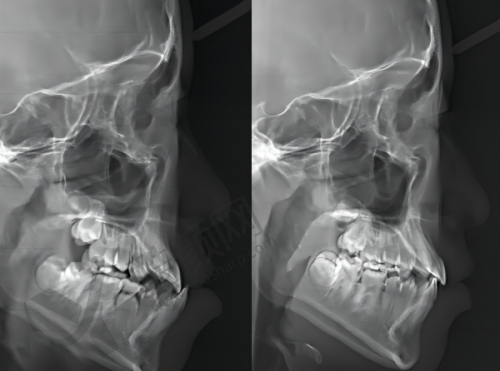

医院借鉴了来自于美国以及德国的成熟口腔检查模式,还吸取了来自于韩国精良的口腔医疗管理经验,在医疗技术的引进方面以及医疗设备的引进等多个方面实现了合作与共享。在设备上,引进了多种精良设备。CBCT机以其三维成像技术,能够清晰地展示口腔结构,帮助医生进行更正确的诊断和治疗规划。全景机则提供了广泛的视野,使得牙科医生可以全方面评估患者的口腔健康状况。超声洁治器利用高频声波技术,能够有效去除牙结石和牙菌斑,降低患者的不适感,提升洁治成效。根管测量仪确保根管治疗的正确度,帮助医生正确测量根管长度,避免治疗中的潜在风险。根管填充器则能够效率高且均匀地填充根管,确保治疗的成功几率。激光设备在口腔治疗中具备舒适、快速的优势,能够有效促进创口愈合,减少术后并发症。